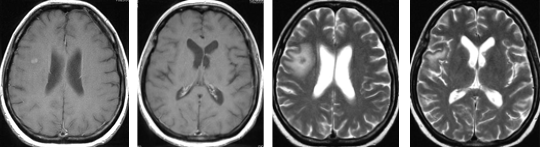

症例 4

腎臓癌による左前頭葉深部白質の転移性小脳腫瘍に対して開頭腫瘍摘出術を施行し全摘しました。脳浮腫の懸念がなくなったため術後ガンマナイフを併用しました。5年以上再発なく経過しています。

症例 5

腎臓癌による右側頭葉の転移性小脳腫瘍に対して開頭腫瘍摘出術を施行し全摘しました。術後ガンマナイフを併用しました。術前に視野障害を自覚しておりましたが、術後改善しました。腫瘍の全摘に加え、機能も回復しました。

腎臓癌の脳転移巣は腫瘍サイズが小さい割に脳浮腫が強い場合が多いです。写真で呈示した如く転移性脳腫瘍の肉眼所見は、血管奇形や血管腫と似ており正常脳との境界がわかりやすいため比較的摘出は容易です。また広範囲な脳浮腫も腫瘍を全摘すると消失します。